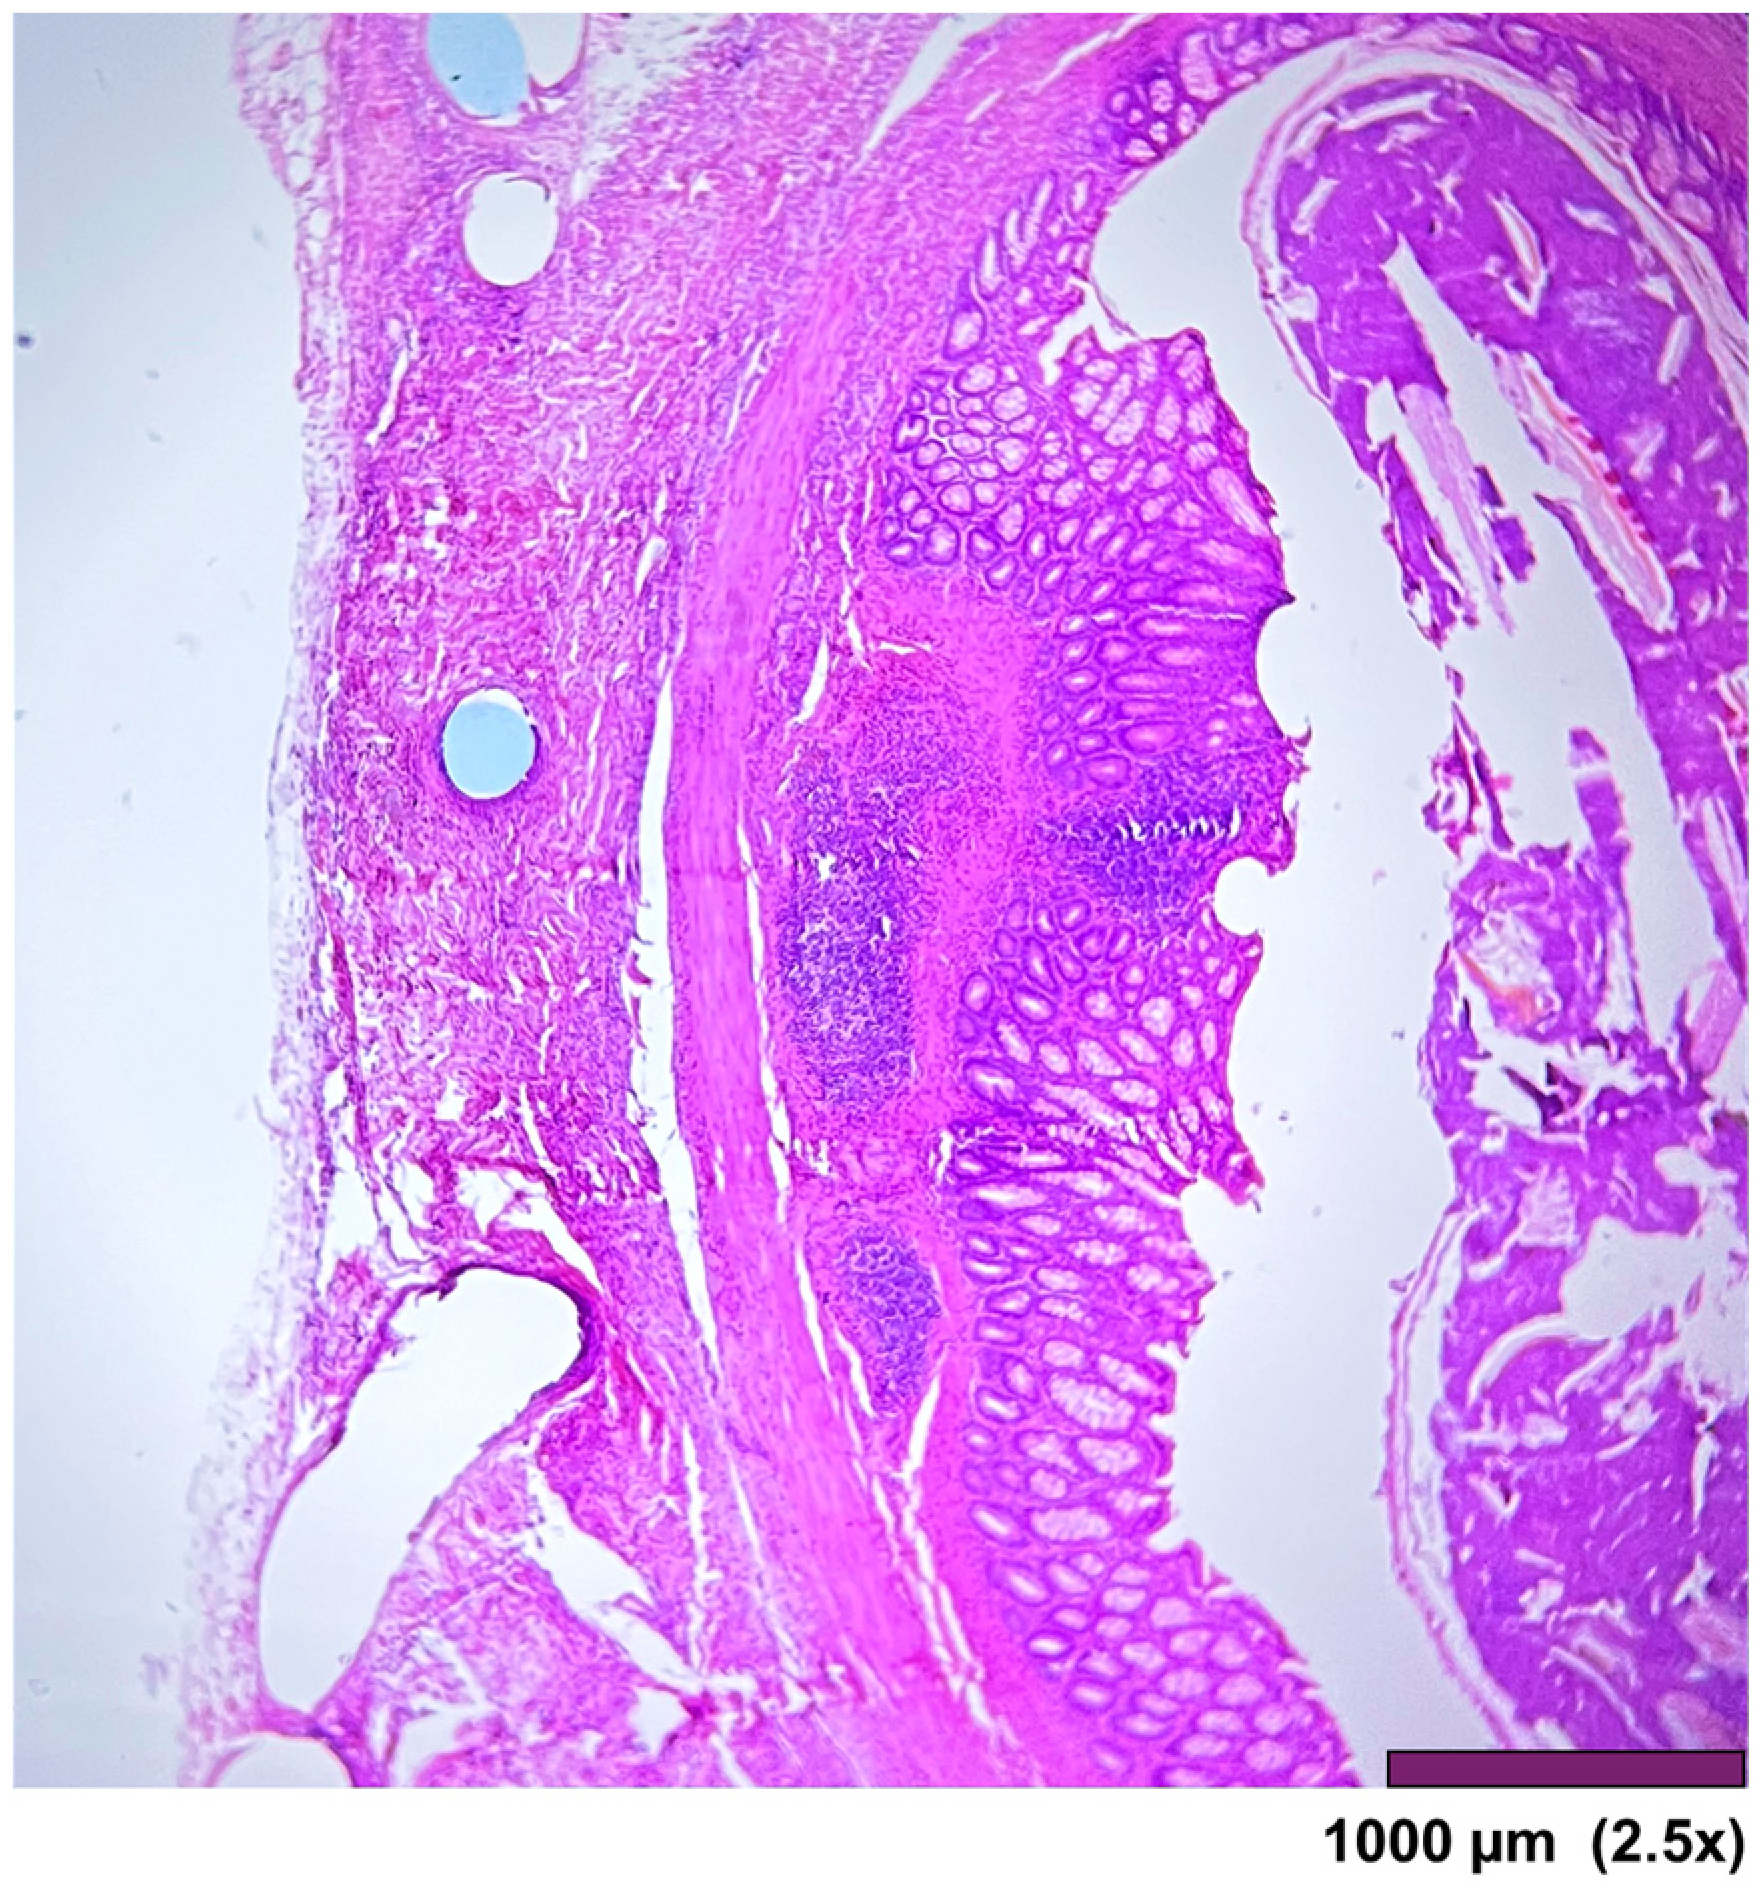

The large intestine wall regenerated completely after surgery, as seen in Figure 9 and Figure 10.

Figure 10. Large intestine: mucosa—top layer, submucosa— between mucosa and muscle layer. The mucosal layer completely covers the anastomosis. The holes in the middle are artifacts due to the removal of the anastomotic sutures (2.5×, HE).